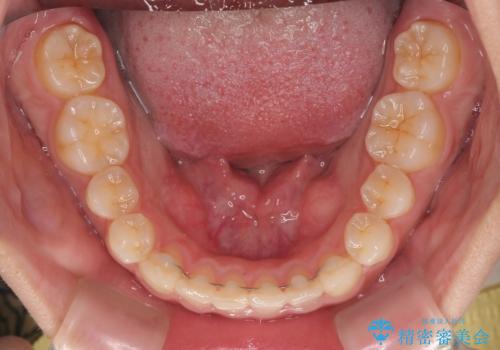

捻れて前に出ている前歯 ワイヤー装置での非抜歯矯正

- 捻れて前に出ている上顎前歯と全体的なデコボコを気にして来院された患者様です。

口元の突出感は強くなかったため非抜歯矯正での対応となりますが、捻転を改善する際に上顎前歯が前突する可能性があったため、上顎臼歯部にアンカースクリューを使用して、歯列が前方に転位しないようにすることとしました。

また舌のトレーニングを行うことで、上顎前歯の突出予防や上下前歯に隙間ができなくなるようにしました。